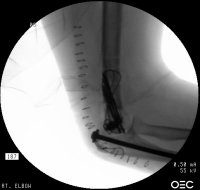

Films on arrival, one week after surgery. Neurovascular exam is normal. Early loss of fixation.

Taking all factors into account, including

• lateral column comminution - preventing solid plate fixation,

• the large screw occupying the central column could not be replaced by any screw small enough to engage a plate - preventing plate fixation,

the operating surgeon decided to achieve stability with triple tension band fixation and bone graft:

A triangle of tension bands was constructed using 1.6 and 2.0 mm pins, with the most distal pin transfixing all four distal fracture fragments. It would have been possible to add a wire through the center of the cannulated screw for an additional cerclage proximally, but this was not done because of concerns regarding corrosion at the titanium/stainless contact point. Although one pin appears to be within the old cannulated screw, it is not.